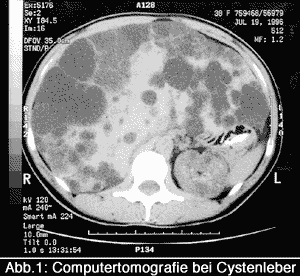

Die familiäre Anamnese spielt für die Diagnose eine wichtige Rolle. Die entscheidende Frage bei der Einschätzung der Erkrankung ist die Beurteilung der Lebergröße, so dass, um dies zu klären, Bild gebende Verfahren wie Abdomensonographie, Computertomographie und die Kernspintomographie angewandt werden. Da durch das Wachstum der Cysten nicht nur das Leberparenchym sondern auch die Gallenwege selten komprimiert werden können, werden Blutuntersuchungen durchgeführt, um eine Störung des Gallenabflusses festzustellen.